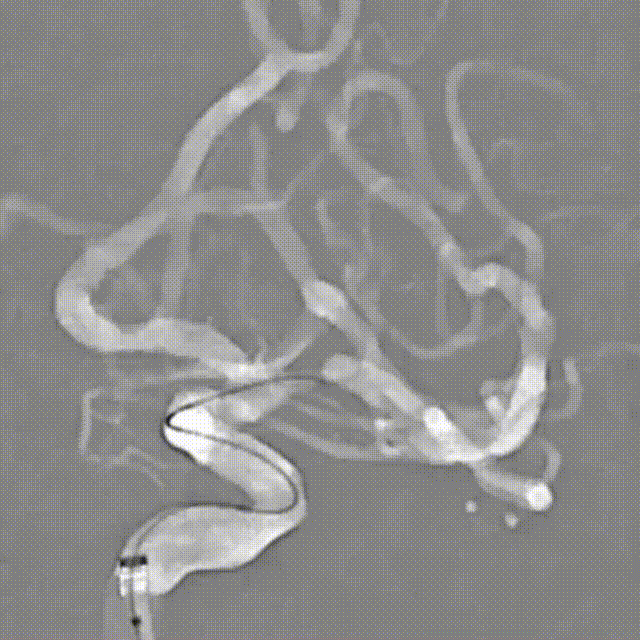

复查造影显示支架贴壁可,狭窄明显改善,远端颅内血管无明显缺失。

➢支架释放后标准正侧位造影